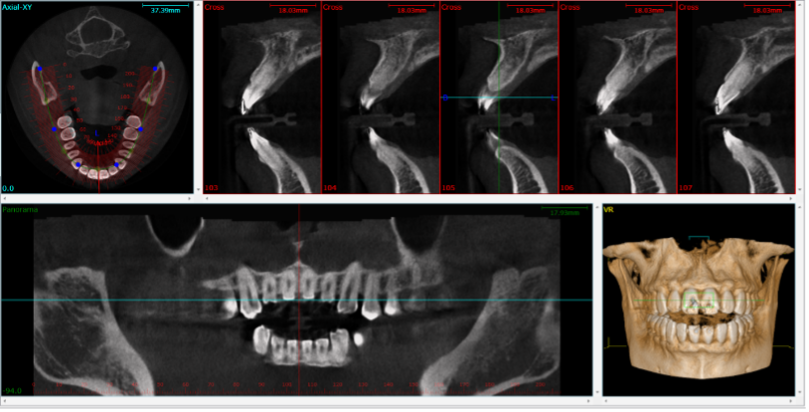

Different images from a single CBCT acquisition (image courtesy of Wikipedia Commons / Public Domain)